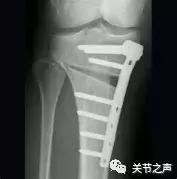

截骨畸形矫正术(HTO):主要适用于关节退变程度轻,但关节内翻或外翻畸形明显的病人,这样的病人通过截骨矫正畸形,恢复关节正常的负重后疼痛会随之减轻。